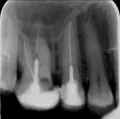

У Вас, скорее всего, воспаление, связанное с некачественным лечением каналов и, похоже, вывод силера за верхушку корня зуба.